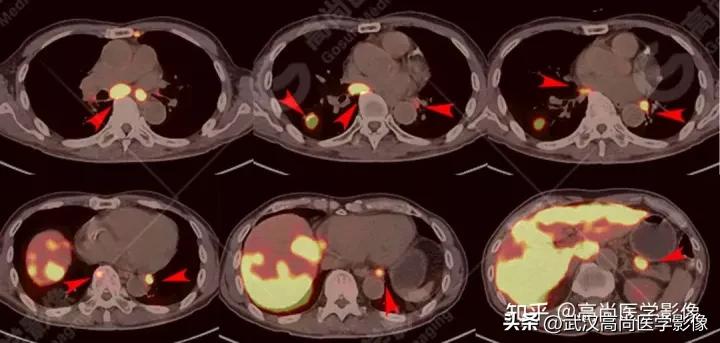

PET/CT寻找原发灶

PET/CT表现:

全身(右侧颈部、双侧锁骨上区、双侧腋窝、右侧胸小肌后间隙、右侧肺门、纵隔、胰腺周围)多发淋巴结肿大,最大约3.8cm×3.3cm,FDG高摄取,SUVmax6.6。

脾脏一低密度结节,FDG高摄取,SUVmax为3.6。

左侧第2、7肋骨质破坏,合并病理性骨折。

右肺上叶后段一实性结节,大小约1.4cm×1.0cm×1.2cm,边缘分叶征、棘状突起,邻近胸膜稍牵拉,FDG高摄取,SUVmax6.6。

高危结节

PET/CT诊断结论

右肺上叶后段周围型肺癌,伴淋巴结、脑、脾脏、肋骨多发转移。